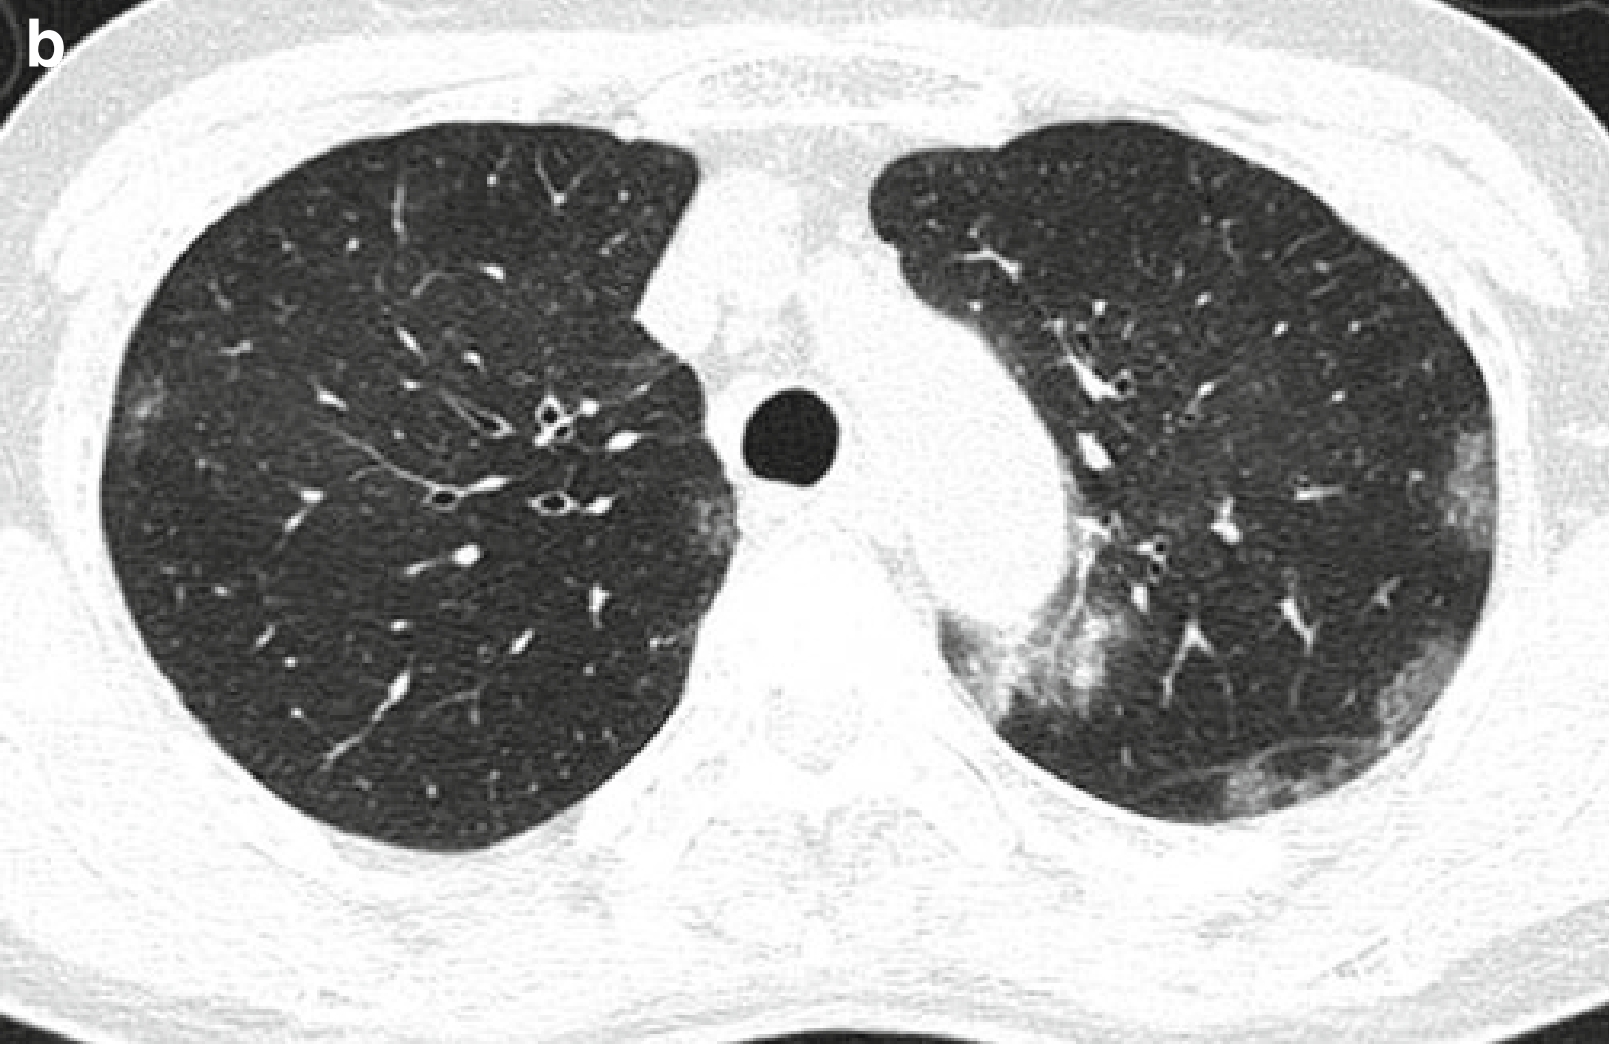

图2 表现为反晕征的隐源性机化性肺炎。

女,58岁。

(a,b)薄层CT扫描(层厚=2.5mm)肺窗分别于肝上下腔静脉水平(a)和右膈顶水平(b)示双肺多发磨玻璃密度病灶,并可见反晕征(箭头所示)。

(c)低倍光镜(×8)下可见稍密集的实变区域(箭头所示)及有炎症细胞浸润的相对松散的间质区(空心箭头所示),这些密集区与相对松散区,形成了反晕征。

(d)高倍光镜(×100)下可见:在呼吸性细支气管、肺泡管和肺泡内见由成纤维细胞组织构成的多发息肉(箭头所示)。由于单核细胞浸润,肺间质中度增厚。